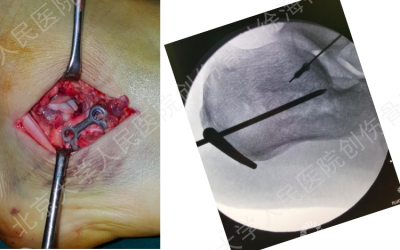

方案分享

徐教授的方案

经跗骨窦小切口显露和复位距下关节

纠正跟骨结节骨块的内翻

经皮下隧道植入钢板

螺钉数量:三点固定原则

“三点”支撑固定